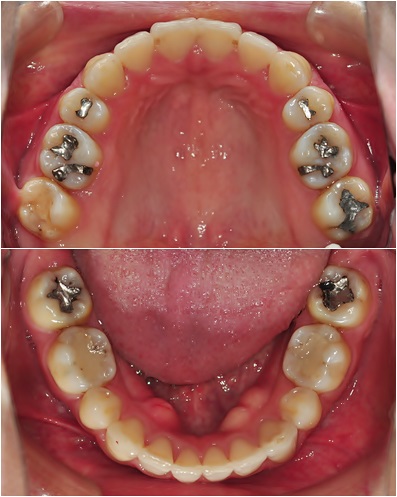

유지장치 붙이기 전 치아 사진입니다~ 오홋~ 정말 가지런해진 치아~ + ㅁ+)!!

상악, 하악 둘 다 치아 안 쪽에 고정식 유지장치 붙였어요~ ^^ 이렇게 붙인답니다~